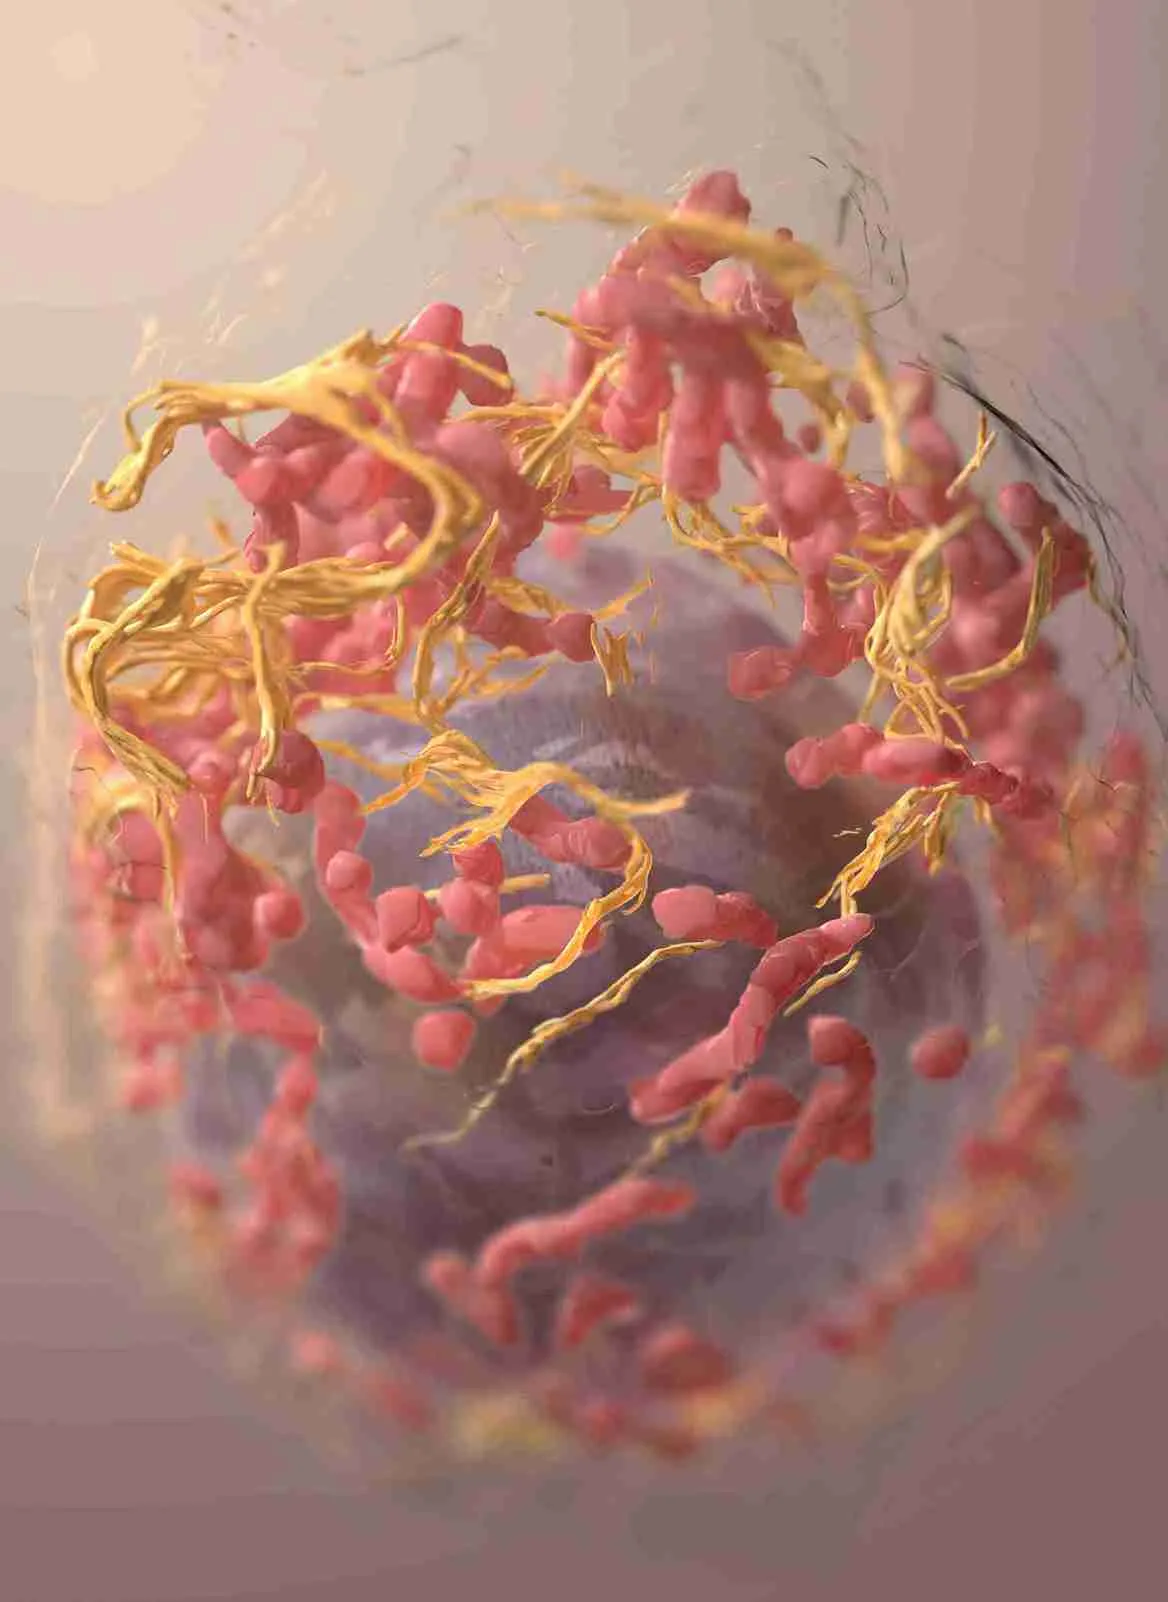

However, when LDL levels become elevated, excess cholesterol can accumulate in the walls of our arteries. Over time this buildup forms fatty deposits called plaque. In some cases, plaque can harden and narrow the arteries, a condition known as atherosclerosis. This narrowing reduces blood flow to the heart and other organs, significantly increasing the risk of heart attack, stroke, and peripheral artery disease (PAD).

Imagine LDL cholesterol as packages of cargo being transported throughout the body, and apoB as the unique shipping labels on each package. The more packages circulating (higher apoB level), the greater the risk of them accumulating and causing a blockage in our arteries, leading to atherosclerosis.

The Hidden Killer: Chronic inflammation is like a silent saboteur of cardiovascular health. “The endothelial barrier, in particular, is uniquely vulnerable to damage from inflammation,” says Attia. Imagine your blood vessels as smooth highways; inflammation roughens their surface, creating ‘potholes’ where cholesterol particles (the metaphorical cars) are more likely to get stuck, initiating the process of atherosclerosis.

Lp(a): Lipoprotein(a), or Lp(a), is a modified form of LDL with a unique ‘sticky’ structure. Attia describes the dangers of Lp(a): “As the LDL particle passes through the bloodstream, Lp(a) scoop up bits of oxidized lipid molecules and carry them along. Because of its structure, Lp(a) may be even more likely than a normal LDL particle to get stuck” within blood vessel walls.